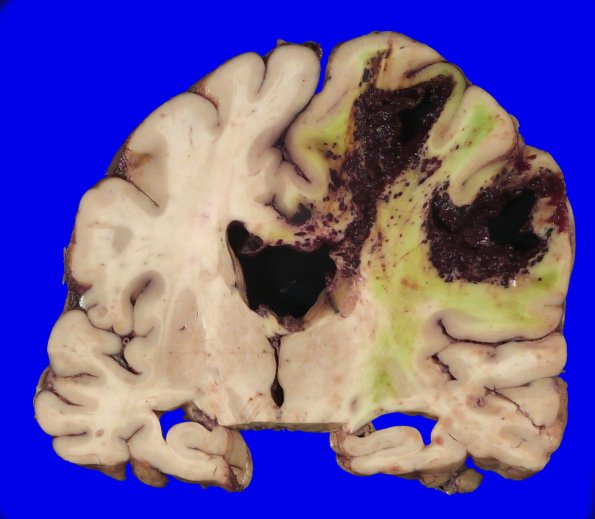

Washington University Experience | VASCULAR | Hemorrhage, hypertensive | 49B4 A20-76_9

This is an unusual hemorrhage for a purely hypertensive pathogenesis; however, this patient has severe coagulopathy superimposed on longstanding cirrhosis and chronic kidney disease.